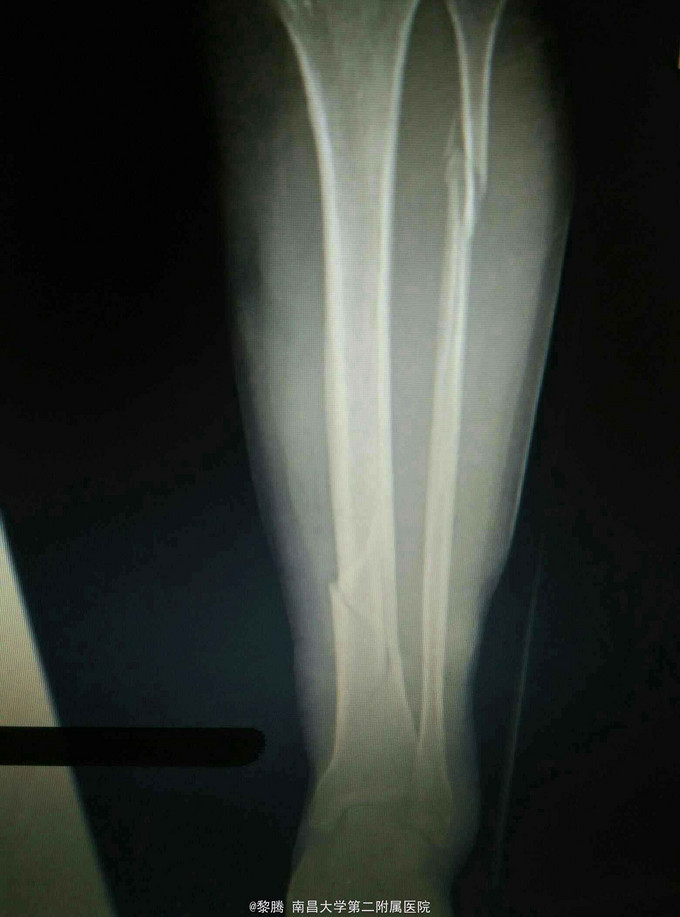

车祸致左小腿肿痛,活动受限8小时 患者中年女性,因车祸致左小腿疼痛、肿胀,伤后当即出现左小腿活动受限,余无特殊不适,急诊入院,行左胫腓骨正侧位片提示左胫腓骨骨折。

查体:左小腿肿胀明显,局部皮肤可见皮下瘀血,左小腿远端压痛明显,可及骨擦感,膝关节主动活动受限,被动活动无明显异常,踝关节主被动活动受限,左足背动脉搏动存在,肢体无明显感觉异常。 辅查:左胫腓骨正侧位片提示左胫腓骨骨折

诊断:左胫腓骨骨折 治疗:胫骨骨折复位内固定